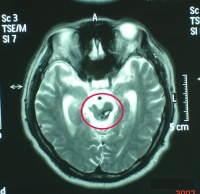

弥漫性轴索损伤(Diffuse axonal injury DAI),系当头部遭受加速性旋转暴力时,因剪应力而造成的神经轴索损伤,病理改变主要位于脑的中轴部分,即胼胝体大脑脚、脑干及小脑上脚等处,多属挫伤、出血及水肿。镜下可见轴索断裂、轴浆溢出。稍久则可见圆形回缩球及血细胞溶解含铁血黄素。最后呈囊变及胶质增生 国外学者提出所谓原发性脑干损伤实际上是DAI的一部分 不应作为一种独立病征。通常DAI均有脑干损伤表现,且无颅内压增高,故需依靠CT或MRI检查才能诊断。

9.MRI 急性颅脑损伤患者通常不作MRI检查。但对病情稳定的弥漫性轴索损伤、大脑半球底部、脑干、局灶性挫裂伤灶和小出血灶、等密度亚急性颅内血肿等,MRI常优于CT扫描。

脑干损伤CT图

脑干损伤与继发性脑干损伤的区别在于症状,体征出现的早晚。继发性脑干损伤的症状、体征皆在伤后逐渐产生。颅内压持续监护亦可鉴别:原发性颅内压不高,而继发性则明显升高。同时,CT和MRI也是鉴别诊断的有效手段。在显示脑实质内小出血灶或挫裂伤方面,尤其是对胼胝体和脑干的细微损害,MRI明显优于CT。脑干听觉诱发电位可以较准确地反映脑干损伤的平面及程度。通常在听觉通路病灶以下的各波正常,病灶水平及其上的各波则显示异常或消失,颅内压监护连续测压亦有鉴别原发性或继发性脑干损伤的作用,虽然二者临床表现相同,但原发者颅内压正常,而继发者明显升高。

2.颅脑CT、MRI扫描 原发性脑干损伤表现为脑干肿大,有点片状密度增高区,脚间池桥池四叠体池及第四脑室受压或闭塞。继发性脑疝的脑干损伤除显示继发性病变的征象外,还可见脑干受压扭曲向对侧移位,MRI可显示脑干内小出血灶与挫裂伤,由于不受骨性伪影影响,显示较CT清楚。